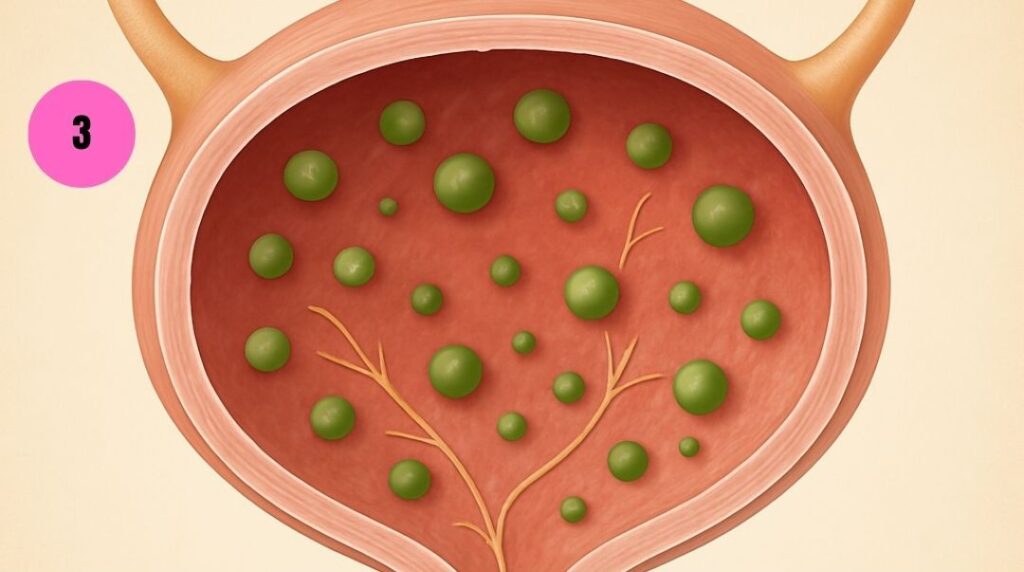

STAGE 3 – REGENERATION

After weeks: protective bacteria repopulate, bladder lining heals, false urgency signals stop, control starts returning.